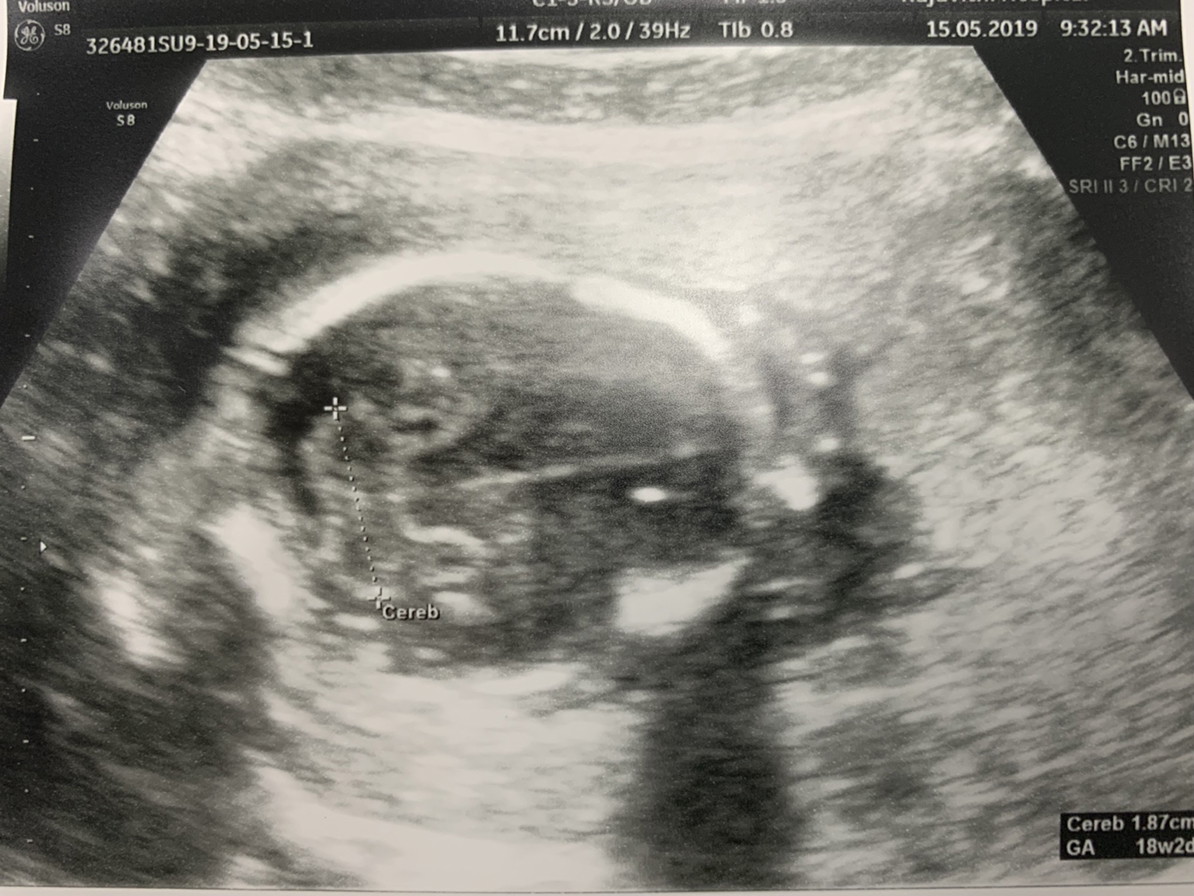

ผช ค่ะ 17 week